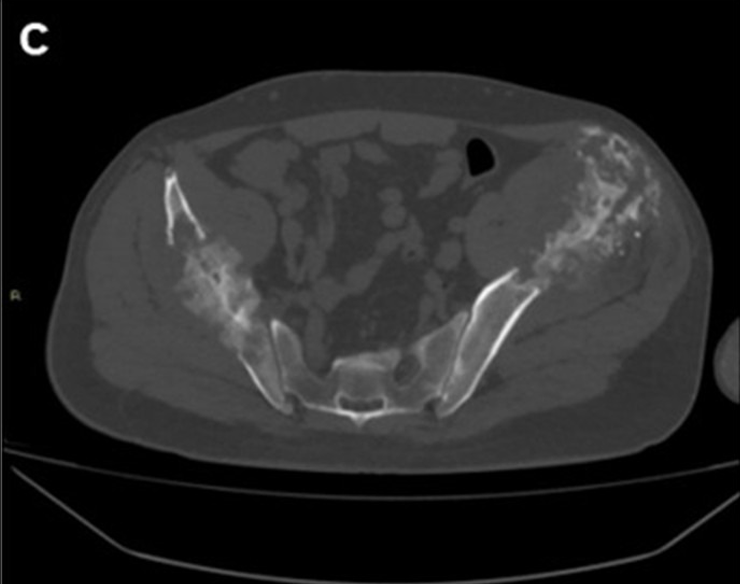

Figure 1: A 56-year-old male patient with two large metastases from renal cancer localized in both iliac bones. (A) panoramic DSA angiogram showing two large hypervascular masses supplied by hypertrophic vessels arising mainly from in internal iliac artery (asterisk). (B) Pre-embolization CT-scan demonstrating the two large lytic lesions of both iliac bones and (C) 6-month follow-up CT showing marked calcification of the lesions.